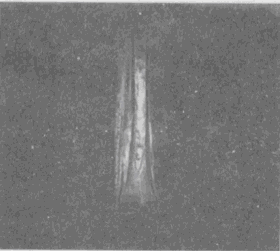

男,33岁,有发热,小腿局部有疼痛,红肿并有压痛,结合图像,最可能的诊断是

男,33岁,有发热,小腿局部有疼痛,红肿并有压痛,结合图像,最可能的诊断是<img border="0" style="width: 324px; height:

[单选题]男,33岁,有发热,小腿局部有疼痛,红肿并有压痛,结合图像,最可能的诊断是A.骨髓炎B.脂肪瘤C.未见异常D.骨髓瘤E.骨化性肌炎

男,33岁,有发热,小腿局部有疼痛,红肿并有压痛,结合图像,最可能的诊断是

[单选题]男,33岁,有发热,小腿局部有疼痛,红肿并有压痛,结合图像,最可能的诊断是A.骨髓炎B.脂肪瘤C.未见异常D.骨髓瘤E.骨化性肌炎

男,33岁,有发热,小腿局部有疼痛,红肿并有压痛,结合图像,最可能的诊断是()

[单选题]男,33岁,有发热,小腿局部有疼痛,红肿并有压痛,结合图像,最可能的诊断是()A . 骨髓炎B . 脂肪瘤C . 未见异常D . 骨髓瘤E . 骨化性肌炎

男,33岁,有发热,小腿局部有疼痛,红肿并有压痛,结合图像,最可能的诊断是()

[单选题]男,33岁,有发热,小腿局部有疼痛,红肿并有压痛,结合图像,最可能的诊断是()A .骨髓炎B .脂肪瘤C .未见异常D .骨髓瘤E .骨化性肌炎